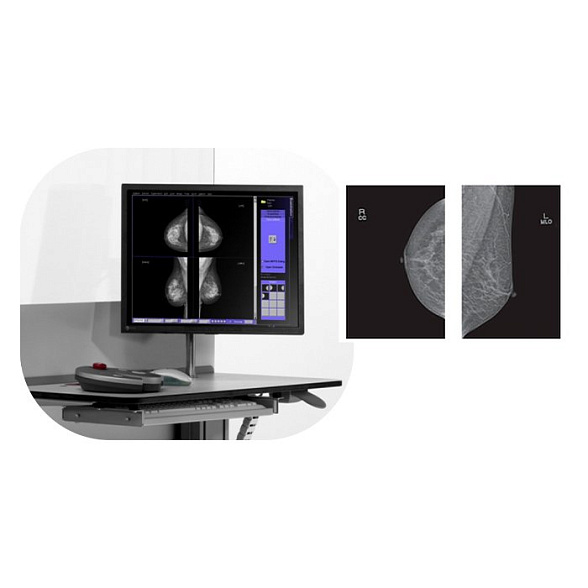

Маммограф PINKVIEW-AT DR Plus Expert Bemems

Маммограф PINKVIEW-AT DR Plus Expert Bemems: Цифровая точность для ранней диагностики

Цифровой маммограф PINKVIEW-AT DR Plus Expert от компании Bemems представляет собой современное диагностическое решение, созданное для проведения высокоточных скрининговых и диагностических исследований молочных желез. Это оборудование сочетает в себе передовые цифровые технологии, эргономичный дизайн и ориентированность на комфорт пациентки, что делает его надежным выбором для оснащения медицинских учреждений.

Ключевым преимуществом системы является прямая цифровая технология (DR) с плоскопанельным детектором, которая обеспечивает получение изображений исключительного качества при минимальной дозовой нагрузке. Это позволяет врачу-рентгенологу выявлять минимальные изменения в тканях на ранних стадиях, что критически важно для успешного лечения.

- Оптимизация рабочего процесса: Мгновенное получение изображения на монитор врача, интеграция с системой архивации и передачи изображений (PACS) и удобное программное обеспечение ускоряют обследование и повышают пропускную способность кабинета.

| Режимы съемки | Стандартные проекции (CC, MLO), при необходимости – дополнительные (например, увеличенная) |

| Программное обеспечение | Специализированное ПО для визуализации, обработки изображений, интеграции с PACS/HIS |